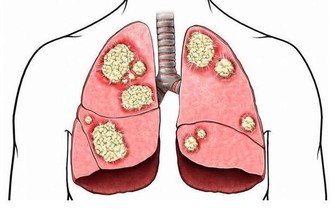

經濟高速發展帶來的嚴重霧霾污染、水體污染及食品中有害物質殘留等因素使得一些癌症,如肺癌、肝癌等的發病率呈逐年上升趨勢。現在,每年全球新發癌症的病人達一千多萬,每年死於癌症的病人超過700萬。無論哪一種癌症,我們最怕聽到的一個詞就是“晚期”,癌症發展到晚期,患者生存的希望相當渺茫,生活質量也難以保證。

6.久治不愈的乾咳或痰中帶血,可見於肺癌。